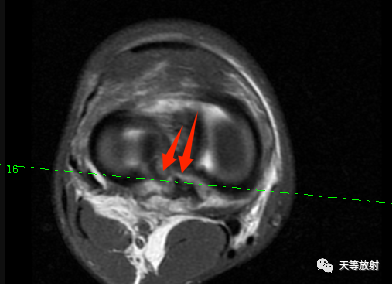

看了又看,觉得半月板应该还有问题:

上图:双后交叉韧带征。提示外侧半月板桶柄状撕裂。

上图:横断位如箭头所指示。